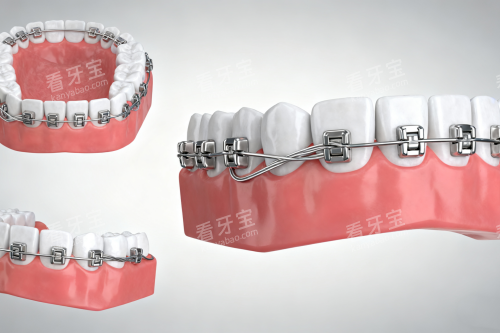

?智能化美学正畸:借助电脑辅助三维诊断进行设计方案,融入美学设计

?儿童早期矫治:针对乳牙期、替牙期错颌畸形,提供MRC肌功能矫治、活动扩弓等干预方案

医院名称金属托槽自锁托槽隐形矫正人民口腔8000元起8000元起19800元起(时代天使)贝壳口腔4880元起--兆博口腔8000元起8000元起19800元起(时代天使)欢笑口腔4800元起7800元起8800元起(全隐形)省钱小贴士: 贝壳口腔和欢笑口腔的金属托槽矫正价格较低,兆博口腔和人民口腔的隐形矫正价格相近。如果预算有限,可以选择金属托槽;如果追求美观,隐形矫正是不错的选择。